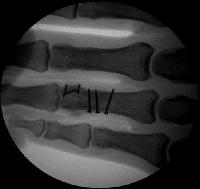

Clinical Example: Proximal phalanx bicondylar oblique volar coronal head fracture

This gentleman sustained a closed severe torsional injury of the right ring finger.

Xrays show a complex intraarticular fracture of the proximal phalanx head. There is a displaced spiral oblique longitudinal fracture with a second oblique coronal split through the articular surface of the radial condyle.